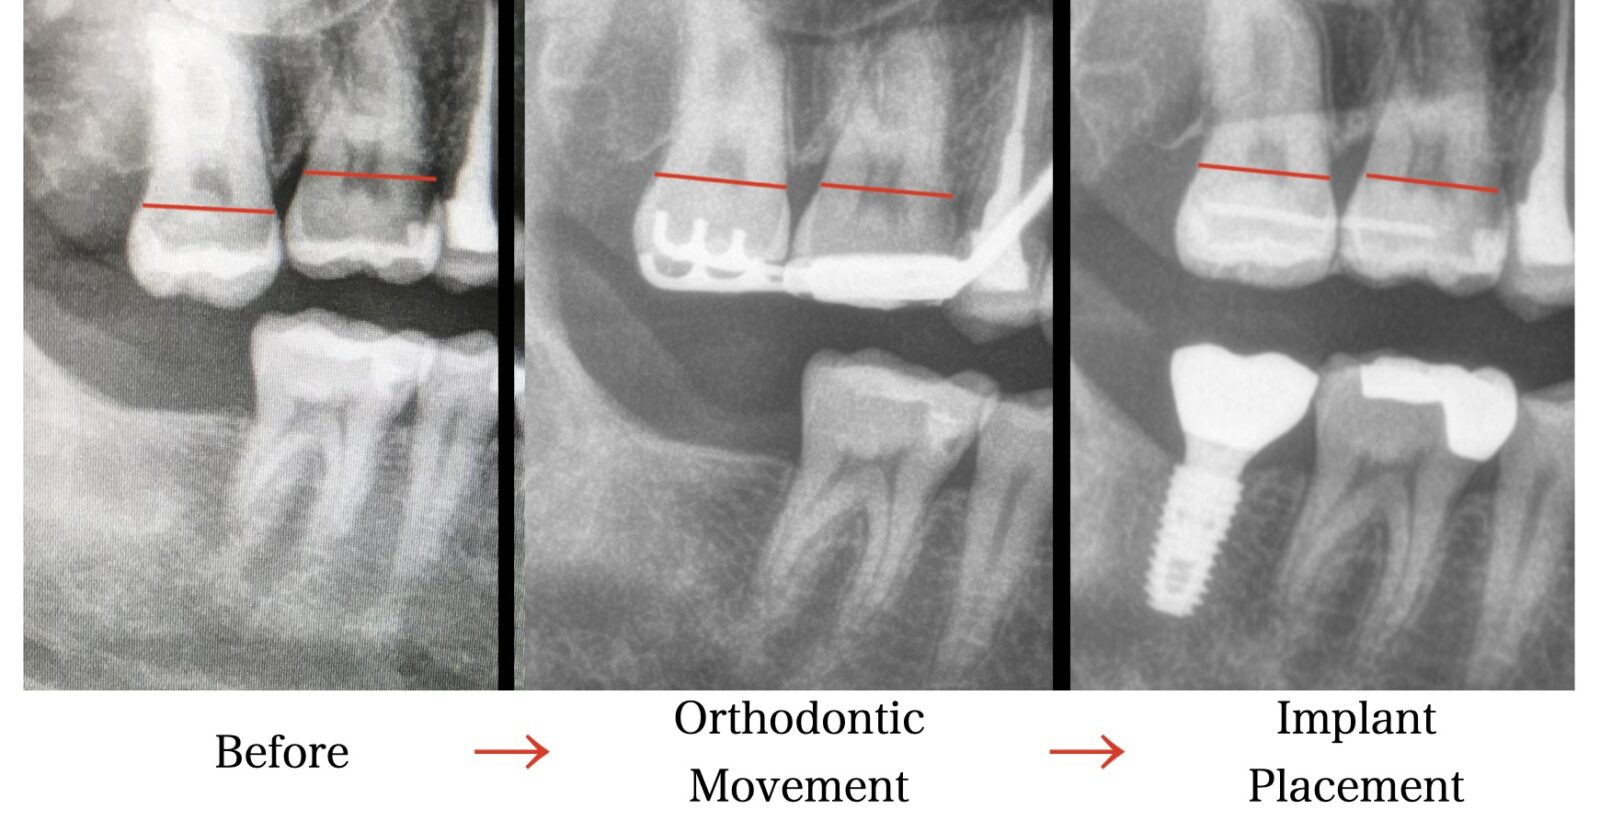

このような場合には、矯正治療を先に行い、歯の位置を整えてからインプラント治療を行うことが多くなります。

このように、矯正治療とインプラント治療はどちらを先に行うかが決まっているわけではありません。